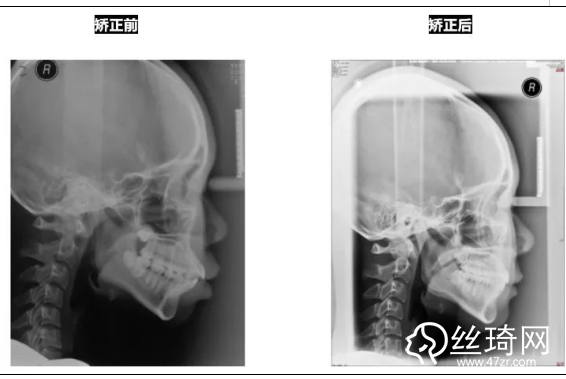

* 影像學檢查分析(以及調(diào)節(jié)前后影像對比):

頭顱側(cè)位片:

前后頭影測量結(jié)果對比: